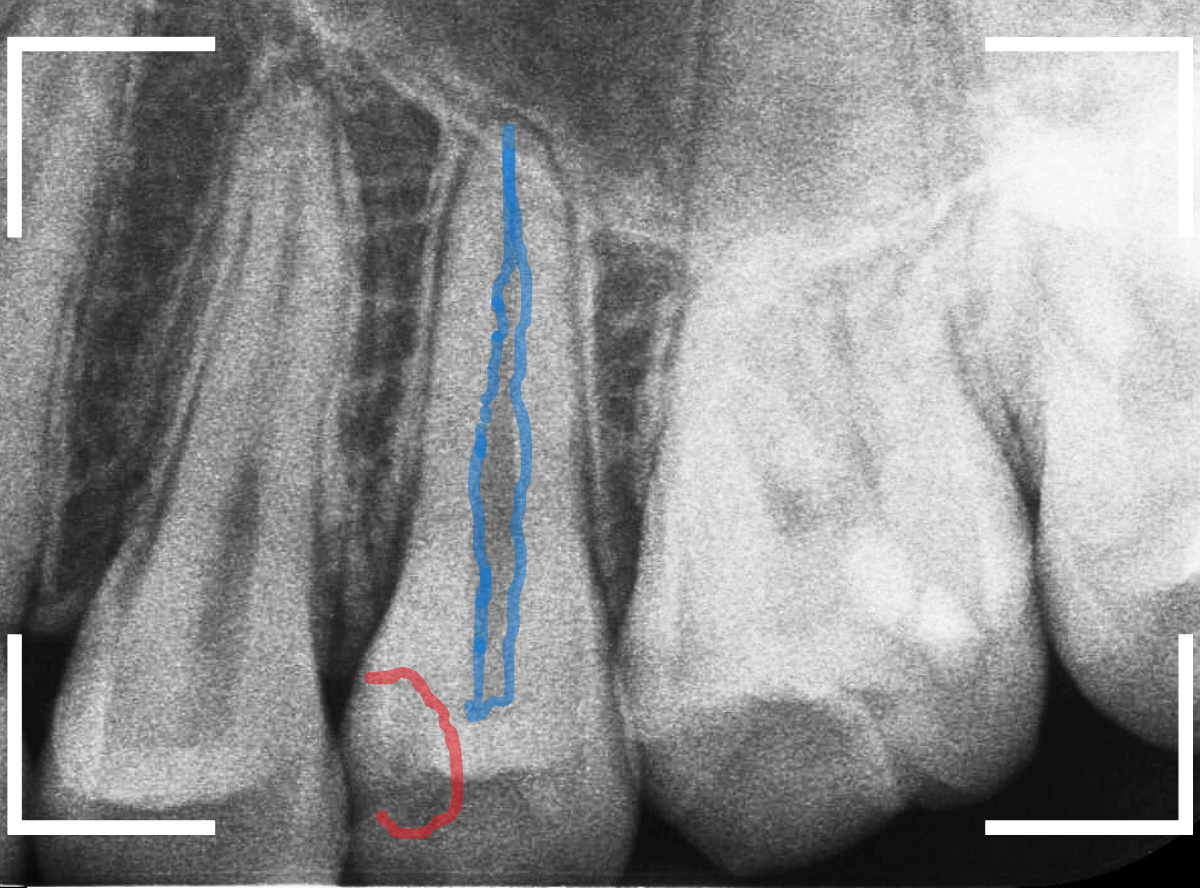

レントゲン写真で確認します。

赤いラインが虫歯と思われる部分、青いラインが歯の神経です。

先ほどの〇部分は明らかな虫歯になっているのがわかります。

この辺りはレジンがつめてありますが、その下もうっすらと虫歯になっていそうです。